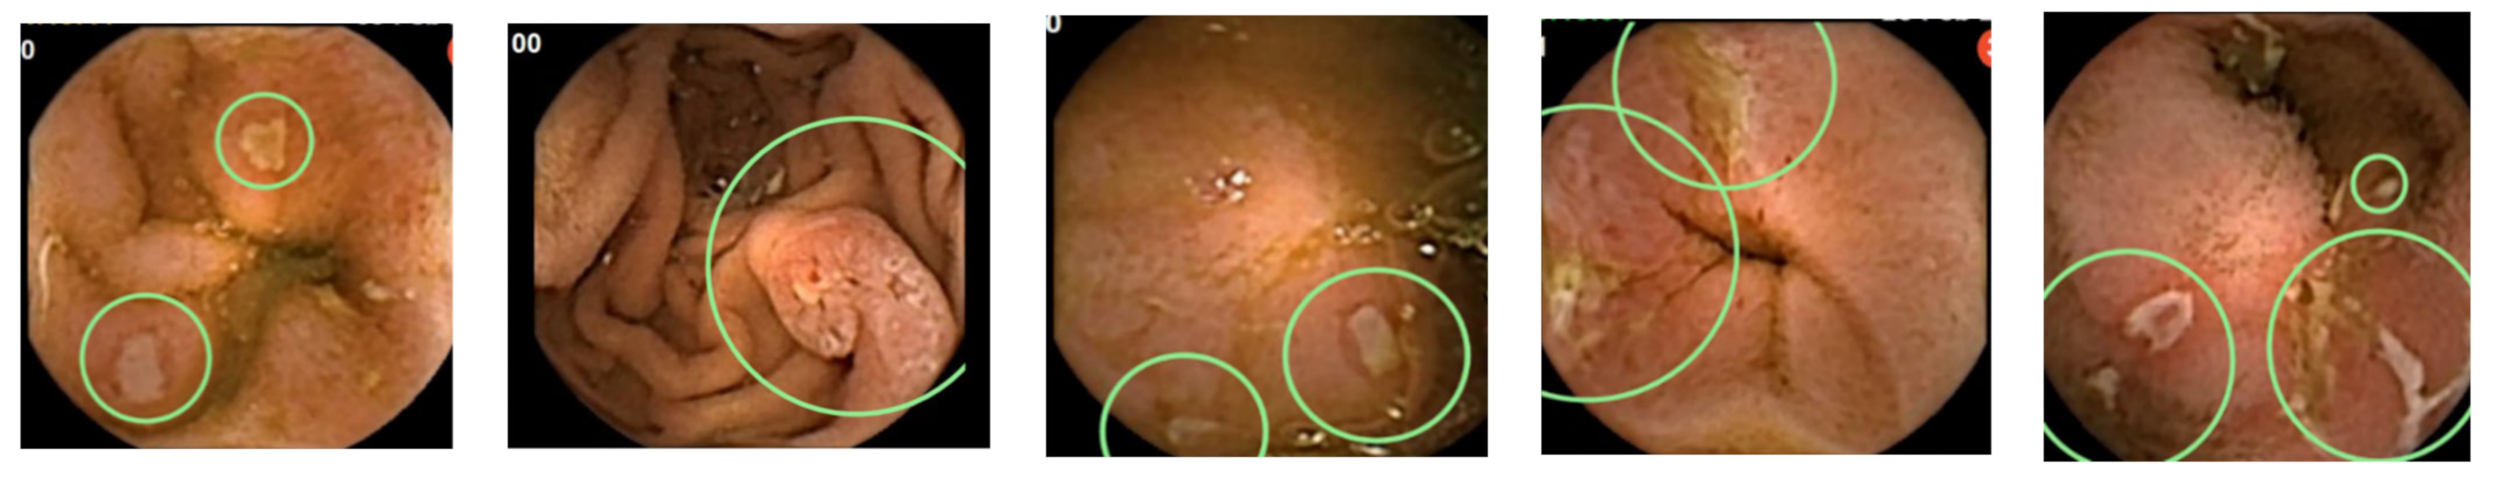

- Klang, E.; Barash, Y.; Margalit, R.Y.; Soffer, S.; Shimon, O.; Albshesh, A.; Ben-Horin, S.; Amitai, M.M.; Eliakim, R.; Kopylov, U. Deep learning algorithms for automated detection of Crohn’s disease ulcers by video capsule endoscopy. Gastrointest. Endosc. 2020, 91, 606–613.e602. [Google Scholar] [CrossRef] [PubMed]